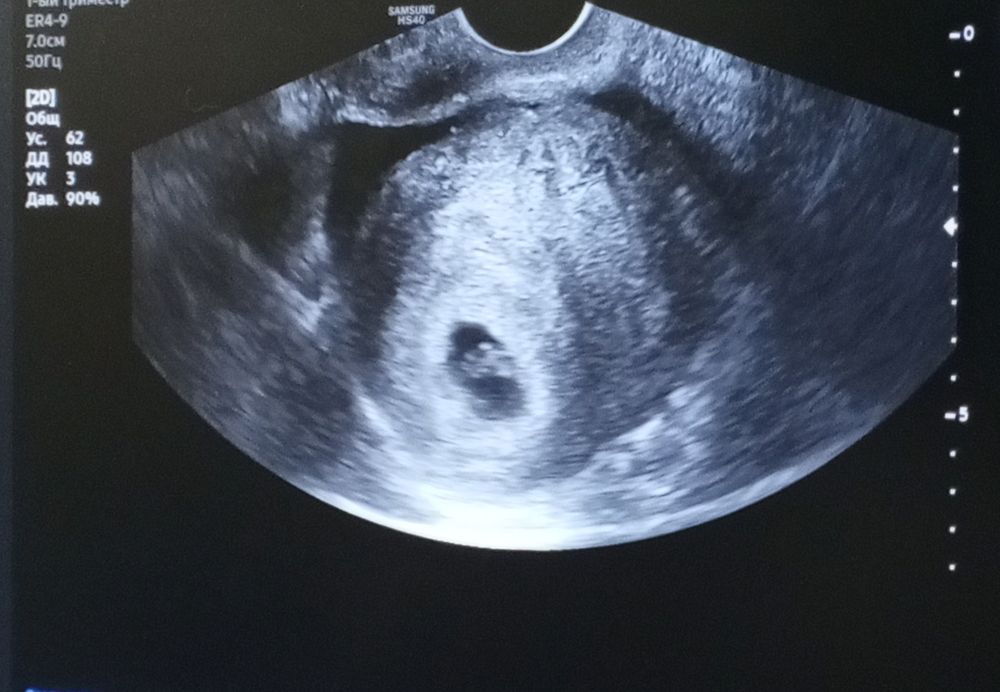

Беременность 6н3д

Сходила на узи, по-началу врач решила посмотреть сверху живота, и ничего не нашла, я уже перепугалась, потом посмотрела изнутри, все нашли, увидели, бусинка в матке, ктр 6.9мм, сердцебиение определяется, жт справа. Теперь я спокойна, моё маленькое счастье 🥰